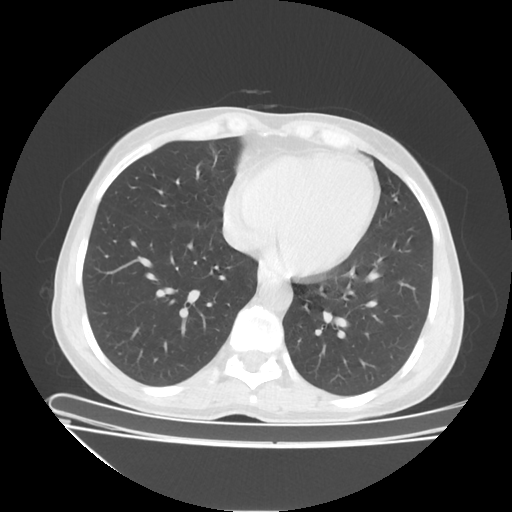

Reconstructed NATIVE CT scan (cycle consistency)

No window - Raw intensity values

Lung window (WL -600, WW 1500 β†’ Low βˆ’1350, High +150)